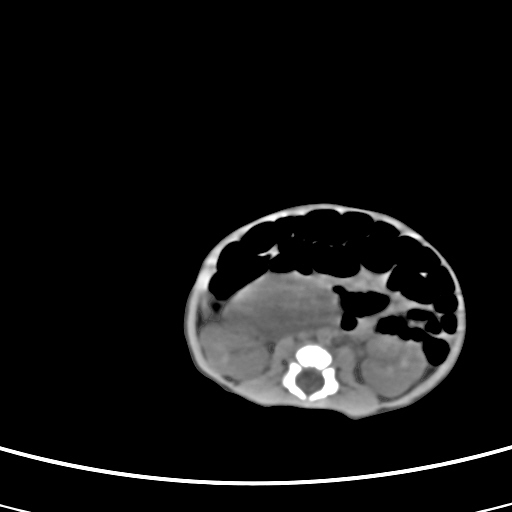

患儿,男性,出生后2天,在胎儿时b超已发现病变,患儿一般情况可。因病变部位偏向于右侧肾上腺区,目前考虑为神经母细胞瘤,不知各位能否支持。

反对定位在右肾上腺区的说法,那么神经母细胞瘤也可以暂时不予考虑。请看下图:

下面这幅图中,似乎可以见到肿瘤的薄包膜,其后与右肾之间的又是什么东西呢?这关系到肿瘤的定位、定性。我考虑病灶是位于肝十二指肠韧带内的畸胎瘤可能性比较大。请各位老师仔细看一下:

病灶巨大,位于右侧肾上腺区,与周围组织分界欠清,内见不规则钙化影,无明显脂肪组织,首先考虑神经母细胞瘤,但畸胎瘤不能排除。

定位后腹膜,定性:畸胎瘤与寄生胎相鉴别.请传骨窗.发现躯干骨或四肢骨就考虑寄生胎.

手术结果为畸胎瘤